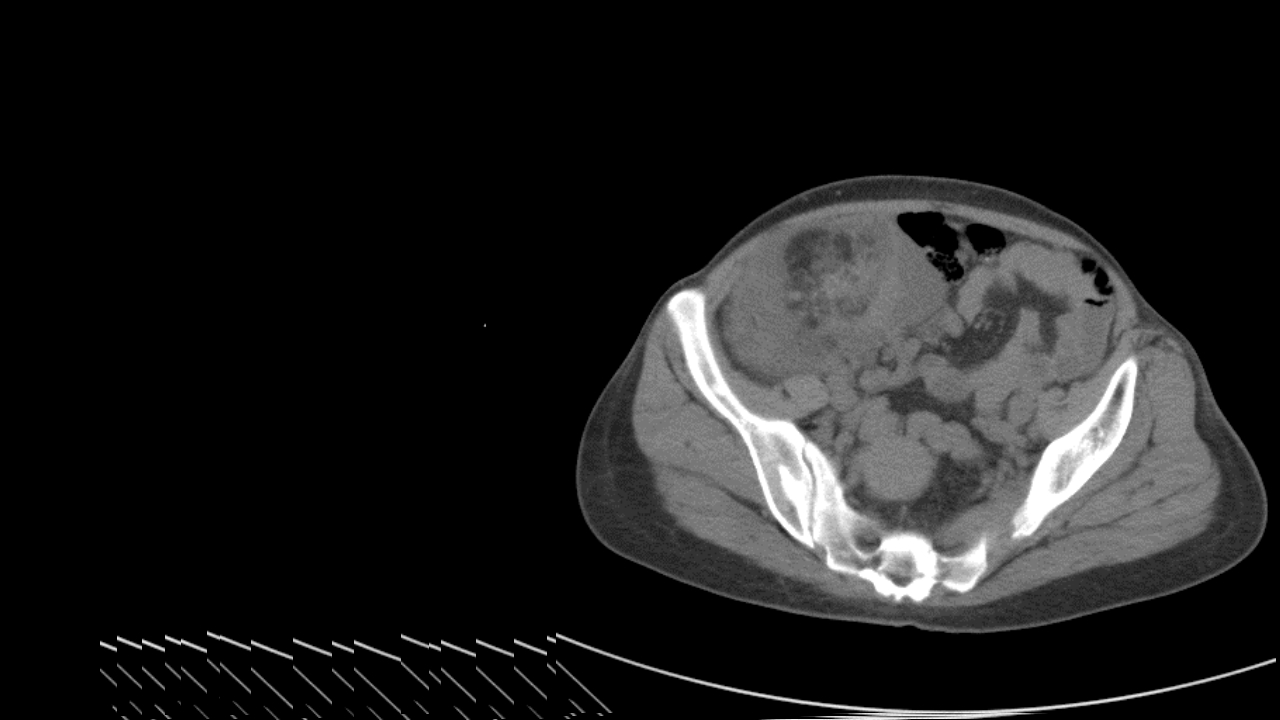

肺淋巴管肌瘤病合并双侧巨大肾血管平滑肌脂肪瘤(X线、CT、MR)